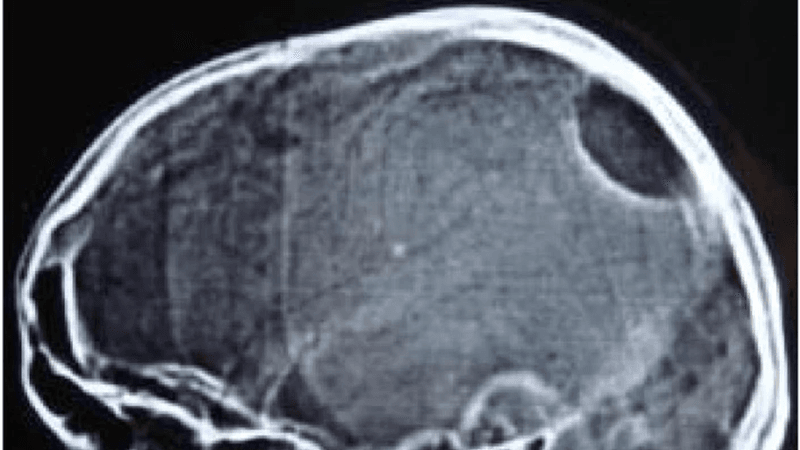

Usually when a person needs an x-ray done, it's to examine a broken arm or leg. In the video below though, doctors found much weirder things lodged in their patients. Scissors, grenades, batteries, wedding rings, chair legs, nails, and bathroom taps are just some of them. Some of the patients were in unfortunate accidents and others were attempting to smuggle things into prison.